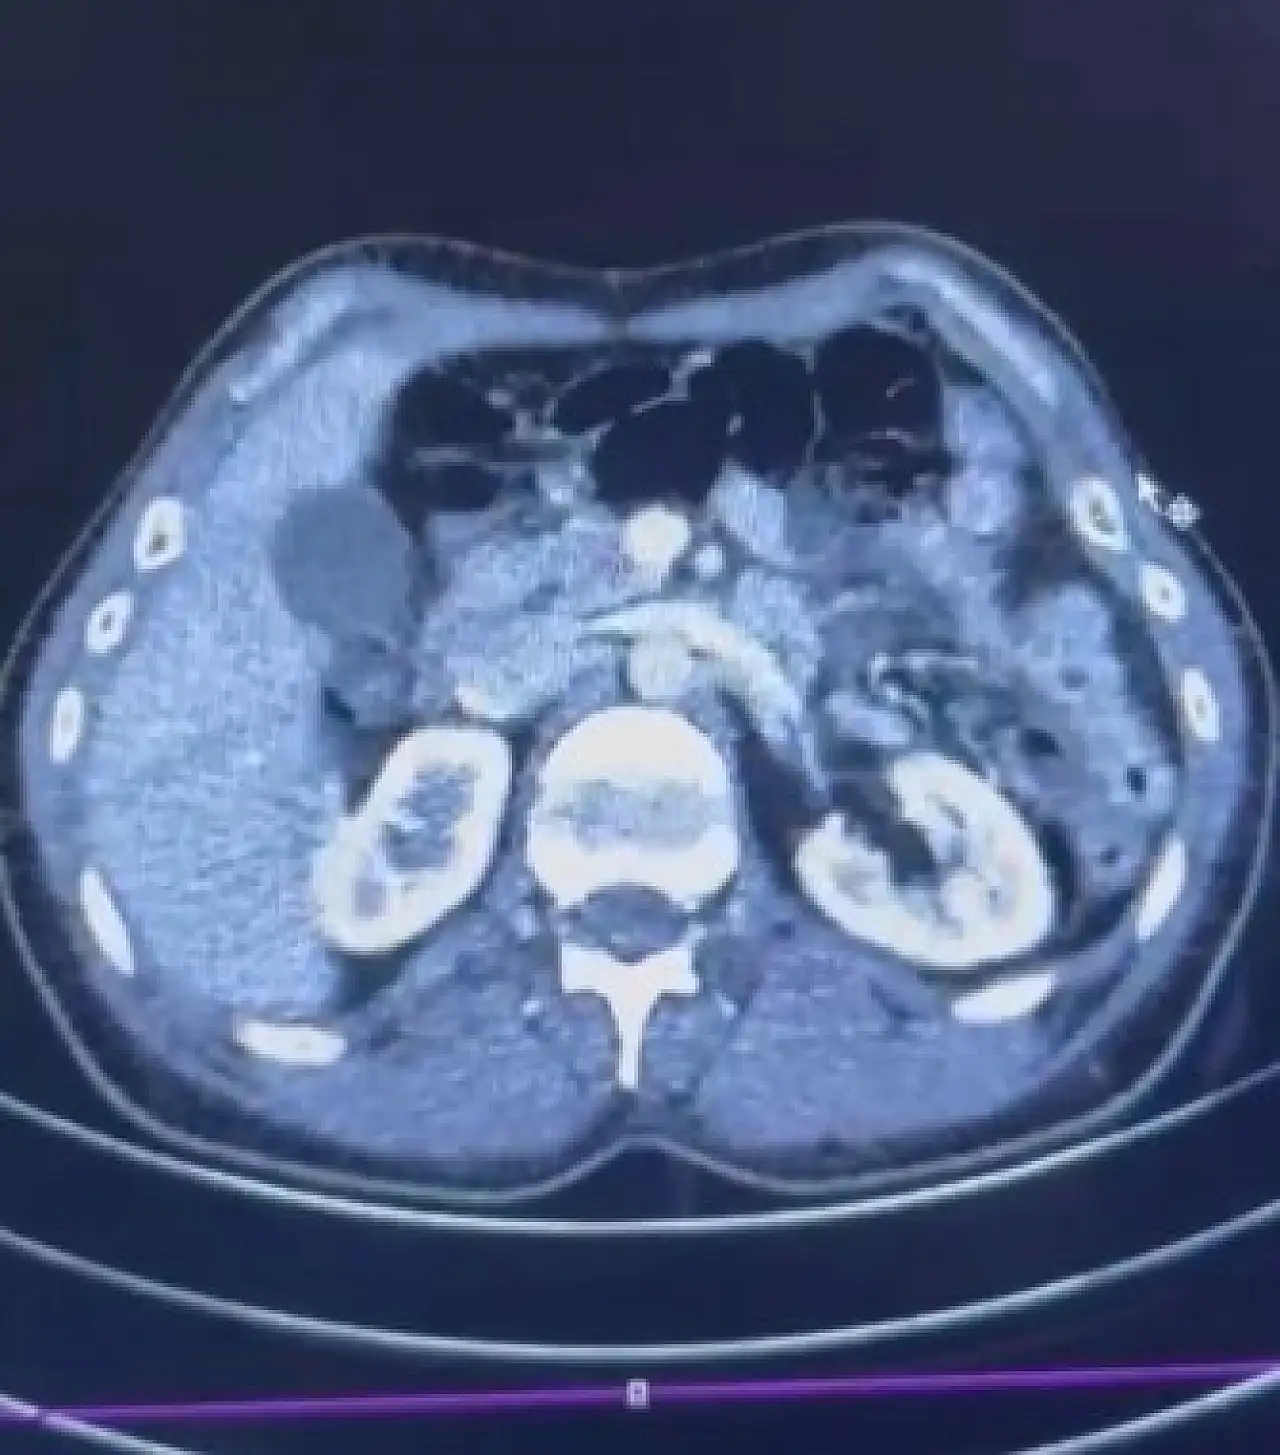

Mide de 554 gram uyuşturucu

Yapılan işlemler kapsamında S.C. ve R.B.C. isimli şahıslar Kayseri Şehir Hastanesinde iç beden muayenesine alındı. Muayenelerde her iki şahsın mide kısmında kapsül hâlinde saklanan uyuşturucu maddeler tespit edildi. Toplam 50 adet kapsül içerisinde 554 gram uyuşturucu madde ele geçirildi.